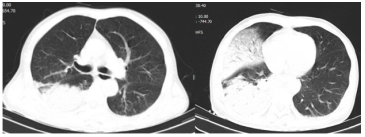

俯卧位8天后,患者Lac逐渐下降,氧合显著改善(图6)。影像学亦可见肺部实变明显改善(图7)

图片

7  俯卧位前后患者胸部影像学对比